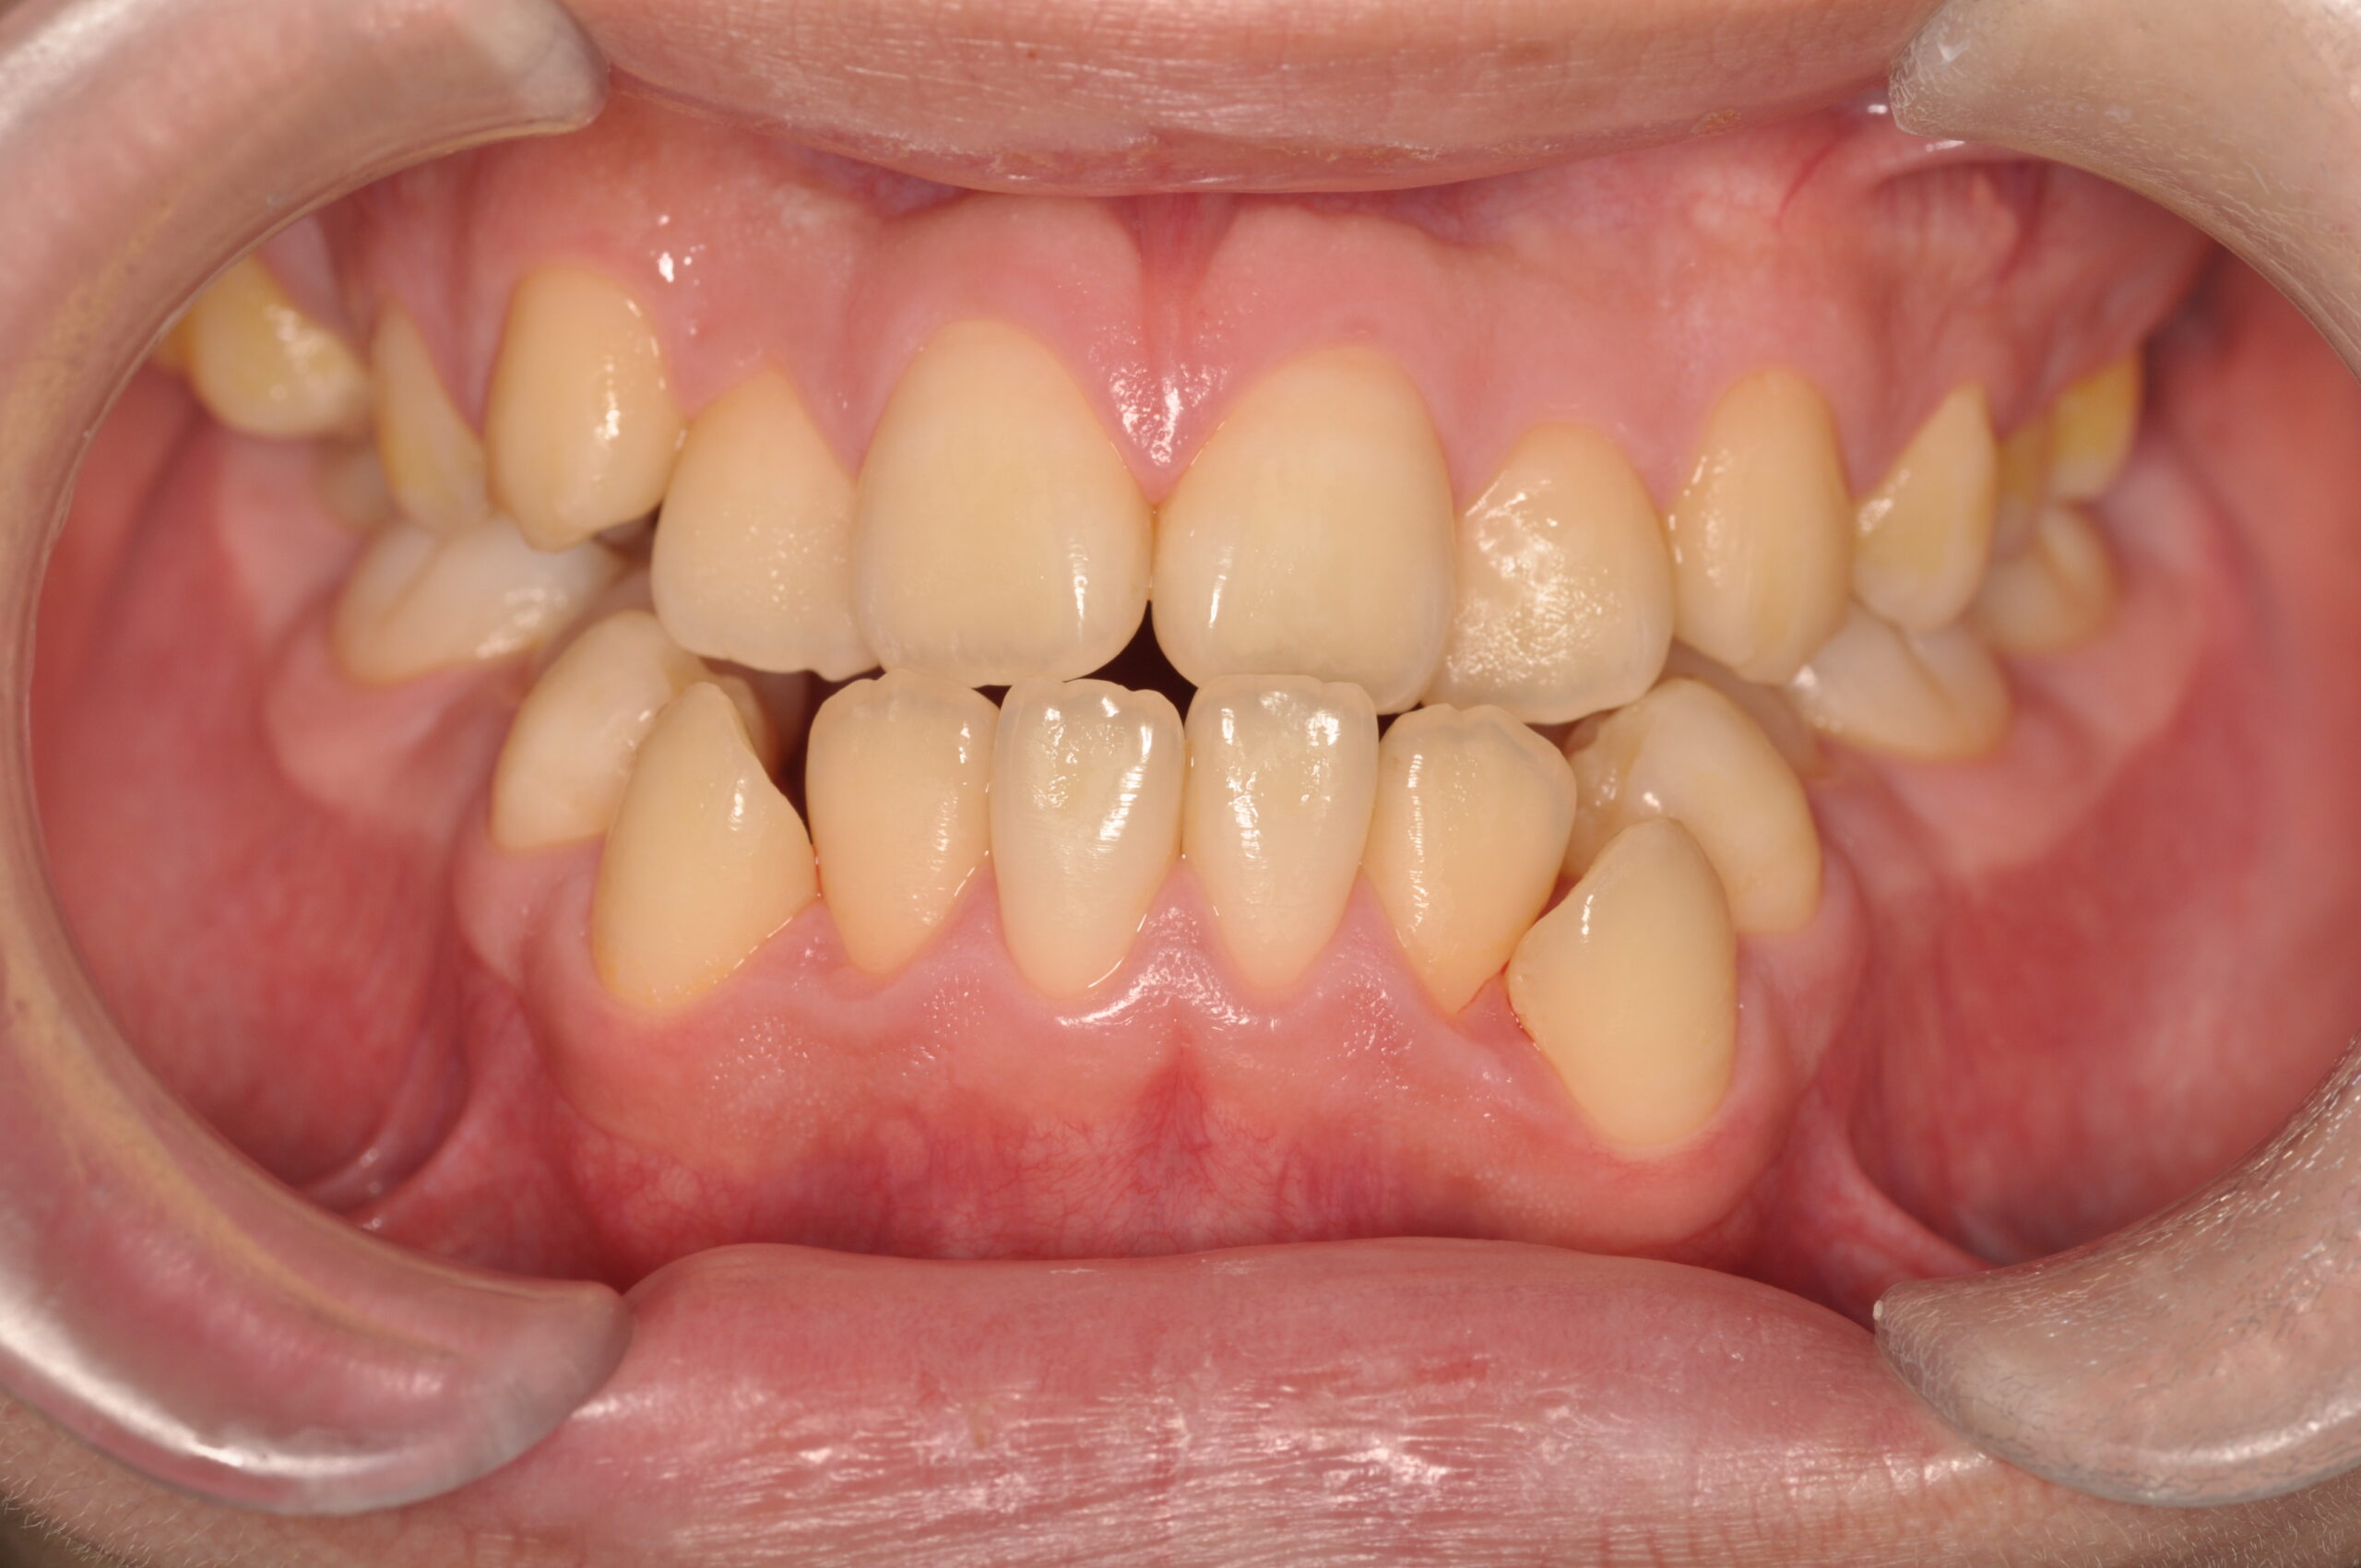

反対咬合(受け口、下顎前突) 叢生

Before

- 骨格性下顎前突症、下顎骨左偏位、叢生、 顎変形症として、外科的矯正術を計画。 叢生、右側第2大臼歯鋏状咬合。 上下顎第一小臼歯を抜歯し、抜歯空隙を利用し叢生を改善し、上下顎それぞれ歯列を整列し、矯正治療中に病院歯科口腔外科にて外科手術(近郊の病院歯科口腔外科にて、口の中から手術、2週間入院)により下顎骨の後退と左偏位の改善をし、適切なオーバージェット、オーバーバイトを付与する。